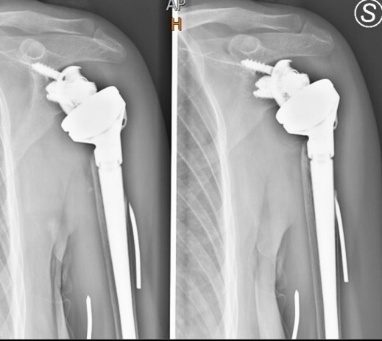

Post-operative radiographs confirmed appropriate implant positioning and restoration of length and version (Figure 2). The patient was placed in an abduction sling and followed a standardized rehabilitation protocol: passive assisted motion began at two weeks, with active exercises at six weeks and strengthening at three months. At three-month follow-up, pain had significantly improved, and active forward elevation reached 100°, with external rotation of 20°. There were no radiographic signs of loosening or migration.

At four-year follow-up, the patient showed excellent functional recovery and a stable implant on plain radiographs with no sign of loosening (Figure 3).